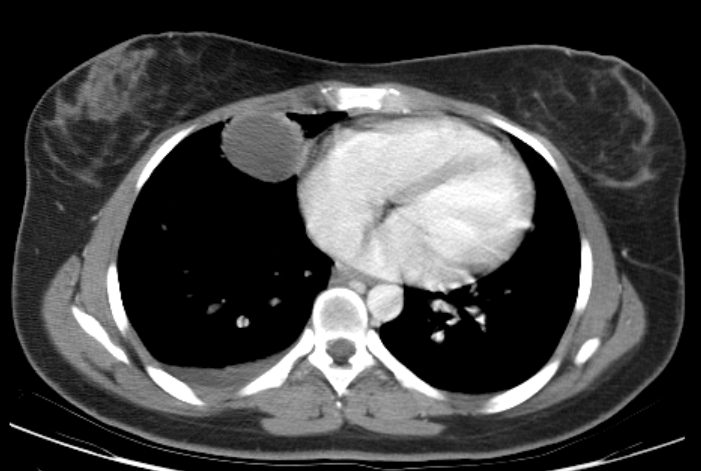

При расположении опухоли в грудной клетке или легких возникают одышка, аритмия.

Как диагностируют тератому

Если подозревают метастазы, то назначают УЗИ, МРТ, КТ, сцинтиграфию, рентгенографию грудной клетки, исследуют кровь на онкомаркеры и другие методы исследования. Если требуется, то назначают анализ крови на хорионический гонадотропин и альфа-фетопротеин. Но точку в том, есть рак или нет, ставят результаты пункционной биопсии и микроскопического исследования материала.

При подозрении на метастазы назначают рентгеноскопию или рентгеноконтрастные исследования для точности диагноза.